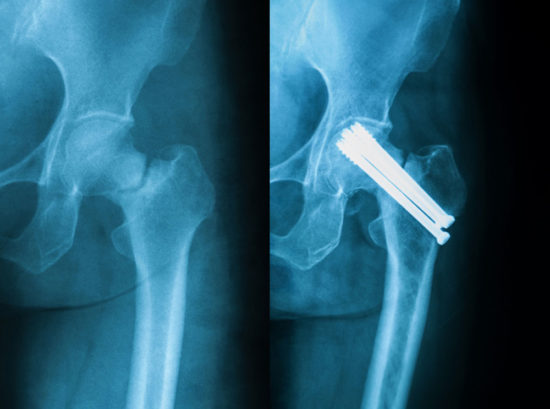

The retrospective cohort study, “Prolonged Opioid Usage Following Hip Fracture Surgery in Opioid-Naïve Older Patients,” followed 29,618 opioid-naïve patients (not filling an opioid prescription 3 months prior to the hip fracture), age 60 and older, who underwent surgical treatment of a hip fracture between 2009 and 2018. The research team, led by Kanu Okike, MD, MPH, FAAOS, used Kaiser Permanente’s Hip Fracture Registry for the study. Because the registry uses a patient’s electronic medical records, the research team was also able to capture relevant factors such as demographics, preexisting comorbidities, and opioid use before, during, and after surgery.

- Prolonged opioid usage was more common following fracture fixation and less common following total hip arthroplasty (both in comparison to hemiarthroplasty).